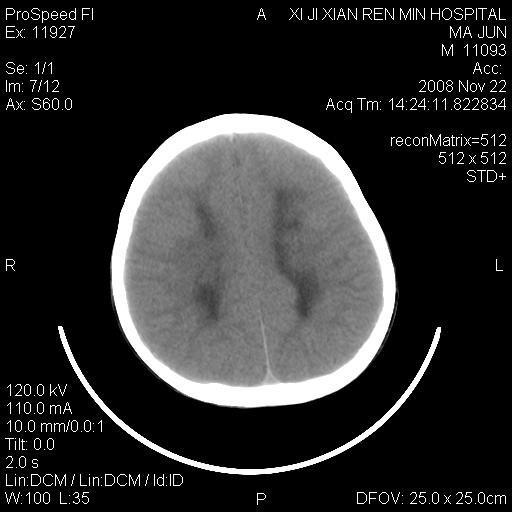

双侧侧脑室前角,三角区旁及半卵圆中心区白质呈低密度改变,半卵圆中心区病灶呈片状融合趋势,无软化征像,脑室无扩张,各神经核团无异常改变,脑皮质无萎缩等征像,结合病史考虑髓鞘发育不良性脑白质病,异染性脑白质营养不良可能性大.不除外多发性硬化等其他改变,建议磁共振检查

脑白质减少,双侧侧脑室额角旁及半卵圆中心可见对称性略低密度影,边缘尚清,考虑脑白质发育不良